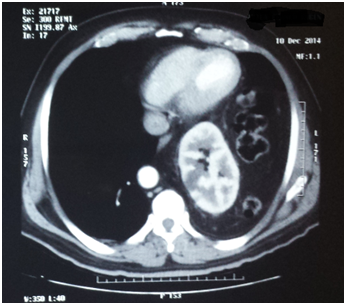

The patient attends the urology outpatient clinic because the previous week he had presented lumbar pain radiating to the right flank as well as the right iliac fossa, intermittent, without fever but with occasional constipation and flatulence. The patient attends to a private’s hospital ER and is prescribed with analgesics, however, 24hours later he presents a new pain condition and attends the same center and undergoes further complete laboratory tests that did not present any alterations. After a throaco abdominal Computerized Axial Tomography with contrast, the presence of intra thoracic ectopic kidney and left diaphragmatic hernia is observed and with a progress caused by the medical treatment administered in the hospital, the patient attends the Urology service due to the presence of left ectopic kidney. Upon arrival to the clinic, the asymptomatic patient does not show any urological pathology and turns out with normal laboratory results (Figure 1-4).

Figure 3 CT sacan show a left kidney near to the heart.